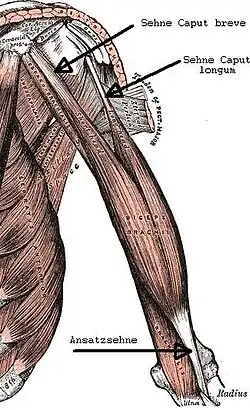

Anatomische Gegebenheiten

Der Musculus biceps brachii weist beim Menschen im Schulterbereich zwei Köpfe auf, daher der lateinische Name biceps (zweiköpfig):

- Caput longum, dessen Sehne vom Tuberculum supraglenoidale – oberhalb des eigentlichen Schultergelenks – durch den Sulcus intertubercularis verläuft. Der lange Kopf ist der primäre Unterarm-Supinator.

- Caput breve, dessen Sehne vom Processus coracoideus (Rabenschnabelfortsatz) des Schulterblatts ihren Ursprung hat. Der kurze Kopf wirkt in erster Linie als Ellenbogen-Beuger.

Beide Köpfe vereinigen sich zu einem Muskelbauch mit einer Sehne in der Ellenbeuge, die sich kurz danach wieder verzweigt und als kräftige Hauptsehne an der im Mittel 22 mm langen und 15 mm breiten Tuberositas radii ansetzt und als Nebensehne über den Lacertus fibrosus (Aponeurosis musculi bicipitis) in die Unterarmfaszie einstrahlt. Die distale Bizepssehne ist im Mittel 22 mm lang und 7 mm dick.